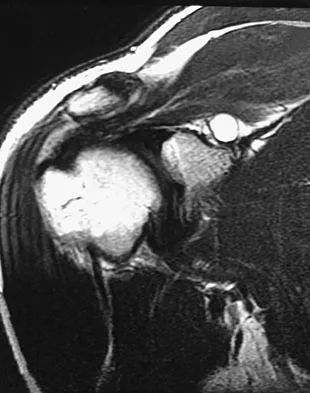

A 72-year-old woman who fell on her right shoulder while using a treadmill is now unable to elevate her right arm. An MRI scan is shown in Figure 7. What is the most likely diagnosis?

The MRI scan reveals a large chronic rotator cuff tear with retraction and fatty infiltration atrophy of the supraspinatus and infraspinatus tendons. This tear is responsible for the patient's severe weakness and inability to elevate the arm.